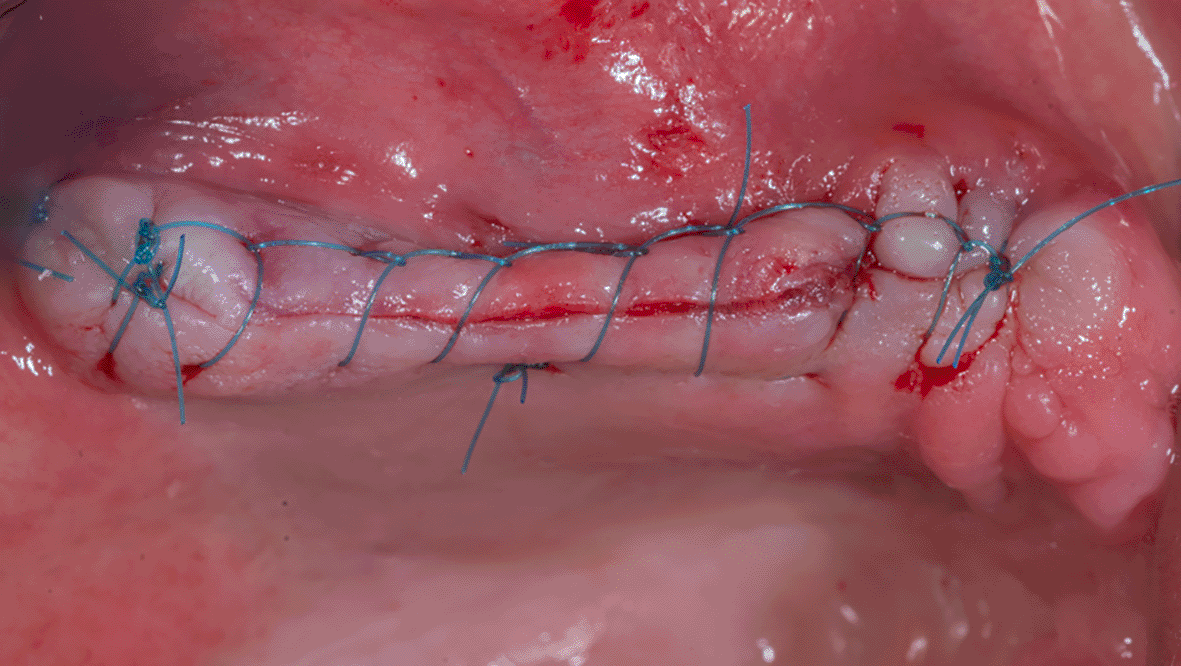

The mucoperiosteal flap is then repositioned and sutured ( Figure 9). The patient was given postoperative instructions including not to rinse for 24 hours and to follow a soft diet during the first week after surgery. The patient was also given oral hygiene instructions.

72a8e8c6-ed30-422d-8d84-4a8b8f46f6f2_figure9.gif

Figure 9. The suture of the mucoperiosteal flap.